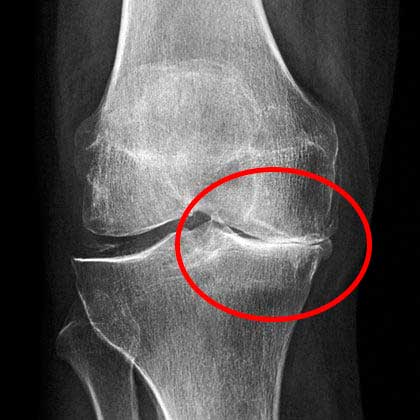

Kondisi lutut saya kala itu. Rasa sakit yang kuat

Di sana dokter melihat hasil rontgen cukup lama, kemudian menyampaikan bahwa saya tidak bisa melakukan pekerjaan fisik lagi dan mengangkat beban dengan berat lebih dari 2 kilo.

X-ray menunjukkan masalah serius dengan lutut saya

Tentu saja, saya sama sekali tidak bisa menerima penyakit ini begitu saja! Bagaimana mungkin saya bisa bekerja setelahnya? Saya sangat mencintai pekerjaan saya, seberat apapun itu. Pada akhirnya, saya memutuskan untuk berkonsultasi dengan dokter lain. Tetapi di sini, saya malah semakin ketakutan! Tanpa menjelaskan diagnosa dengan jelas, beliau langsung mengatakan bahwa saya akan cacat permanen jika tidak melakukan operasi pada lutut saya. Dan biaya operasinya hingga puluhan juta rupiah! Saya tidak memiliki uang sebanyak itu, jadi saya mendaftarkan diri untuk operasi dalam waktu satu setengah bulan ke depan, agar saya bisa mengumpulkan uangnya.

Berikut adalah kondisi lutut saya yang sehat saat ini